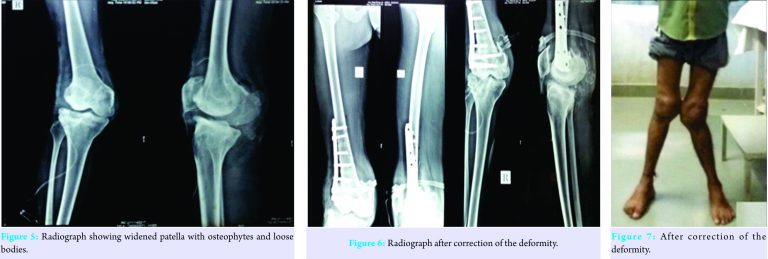

The articular cartilage on medial side was normal, whereas patellar and lateral cartilage was showing Grade III degenerative changes. Patella was widened with lateral osteophytes (Fig. 5) Synovectomy was performed. Majority of loose bodies were removed. From the right knee joint, 5 large loose bodies ranging upto 4 cm in diameter with multiple small loose bodies removed. From the left knee joint, 3 large loose bodies ranging upto 2 cm in diameter with multiple small loose bodies removed. After counselling the patient regarding the need for correction of deformities and possible complication of surgery, he underwent corrective distal femoral osteotomies with plate fixation (Fig. 6) under correction of deformities was performed due to stretching of common peroneal nerve. He developed transient common peroneal nerve palsy on the left leg, which recovered completely after 6 months (Fig. 7, 8).